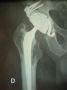

Chirurgie de la hanche à Angers prothèse totale de hancheProthèses totales - nombre de pose en 2018: 300 P.T.H.

Voie d’abord : postérieure - voie de Moore mini-invasive

Externe : Trochantérotomie (Cochin-Paris)

Antérieure : voie Asia mini-invasive sans table orthopédique "la voie qui ne coupe aucun muscle"

Voies antérieures Mini-invasives :Formation avec le Pr De Witt. Même techniques que la voie antérieure de chez Médacta mais sans table orthopédique permettant le réglage exacte de la longueur des deux jambes et évitant les luxations.Récupération chirurgicale rapide ,douleurs minimes en post op immédiat, lever immédiat , sortie au 3 ieme jour.Voir présentation Power point.